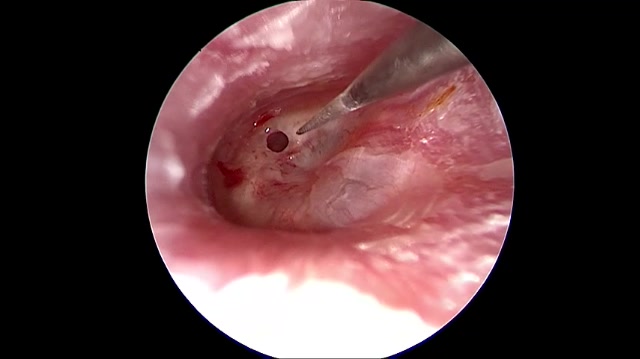

人工耳蜗植入术(含手术视频完整版)

人工耳蜗植入术小经验分享:1.显露砧骨短脚时,在其外侧保留类似屋檐样的一层薄薄的骨质,可以避免磨钻头误触及砧骨而给内耳造成损伤;2.切开圆窗膜时,用5ml或1ml注射器将针尖折弯30-45°,用针尖沿圆窗膜上缘弧形划开,将圆窗膜向下外翻,因注射器是一次性的,其针尖非常锋利,切开圆窗膜时非常好用。